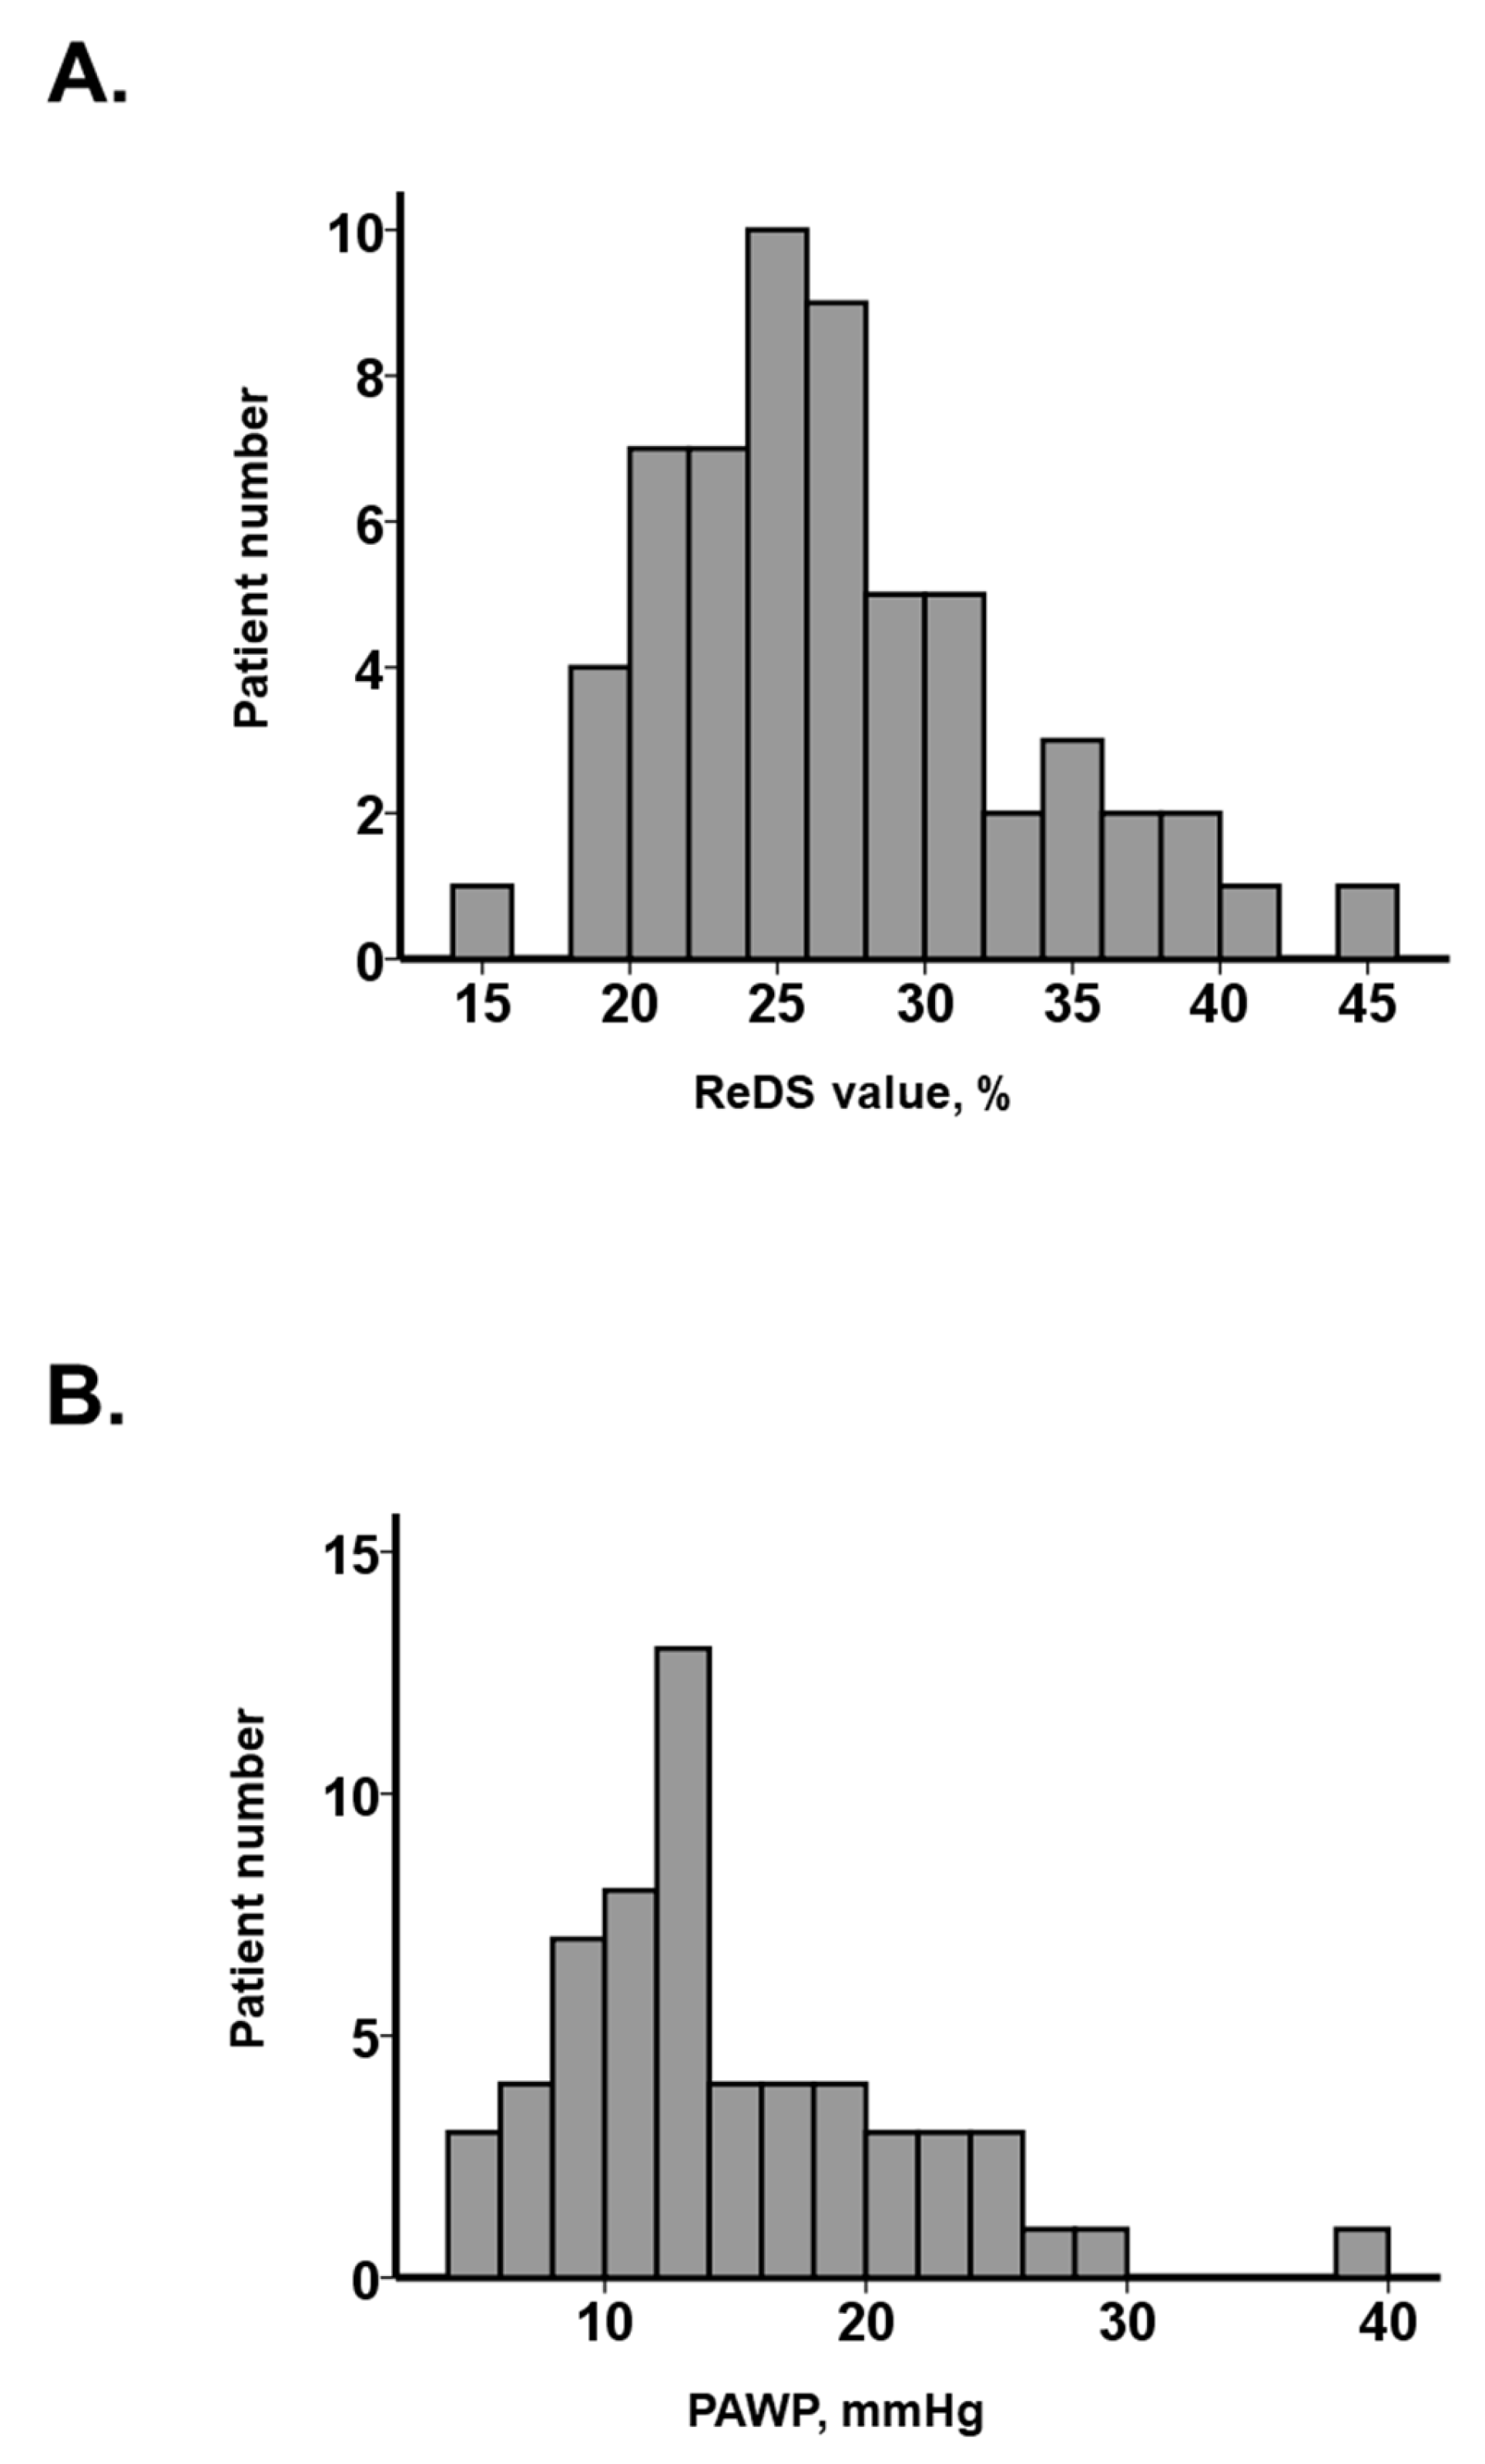

3.1. Baseline Characteristics

3.2. Presence of PE

3.3. Impact of PE on the Relationship between ReDS Values and PAWP